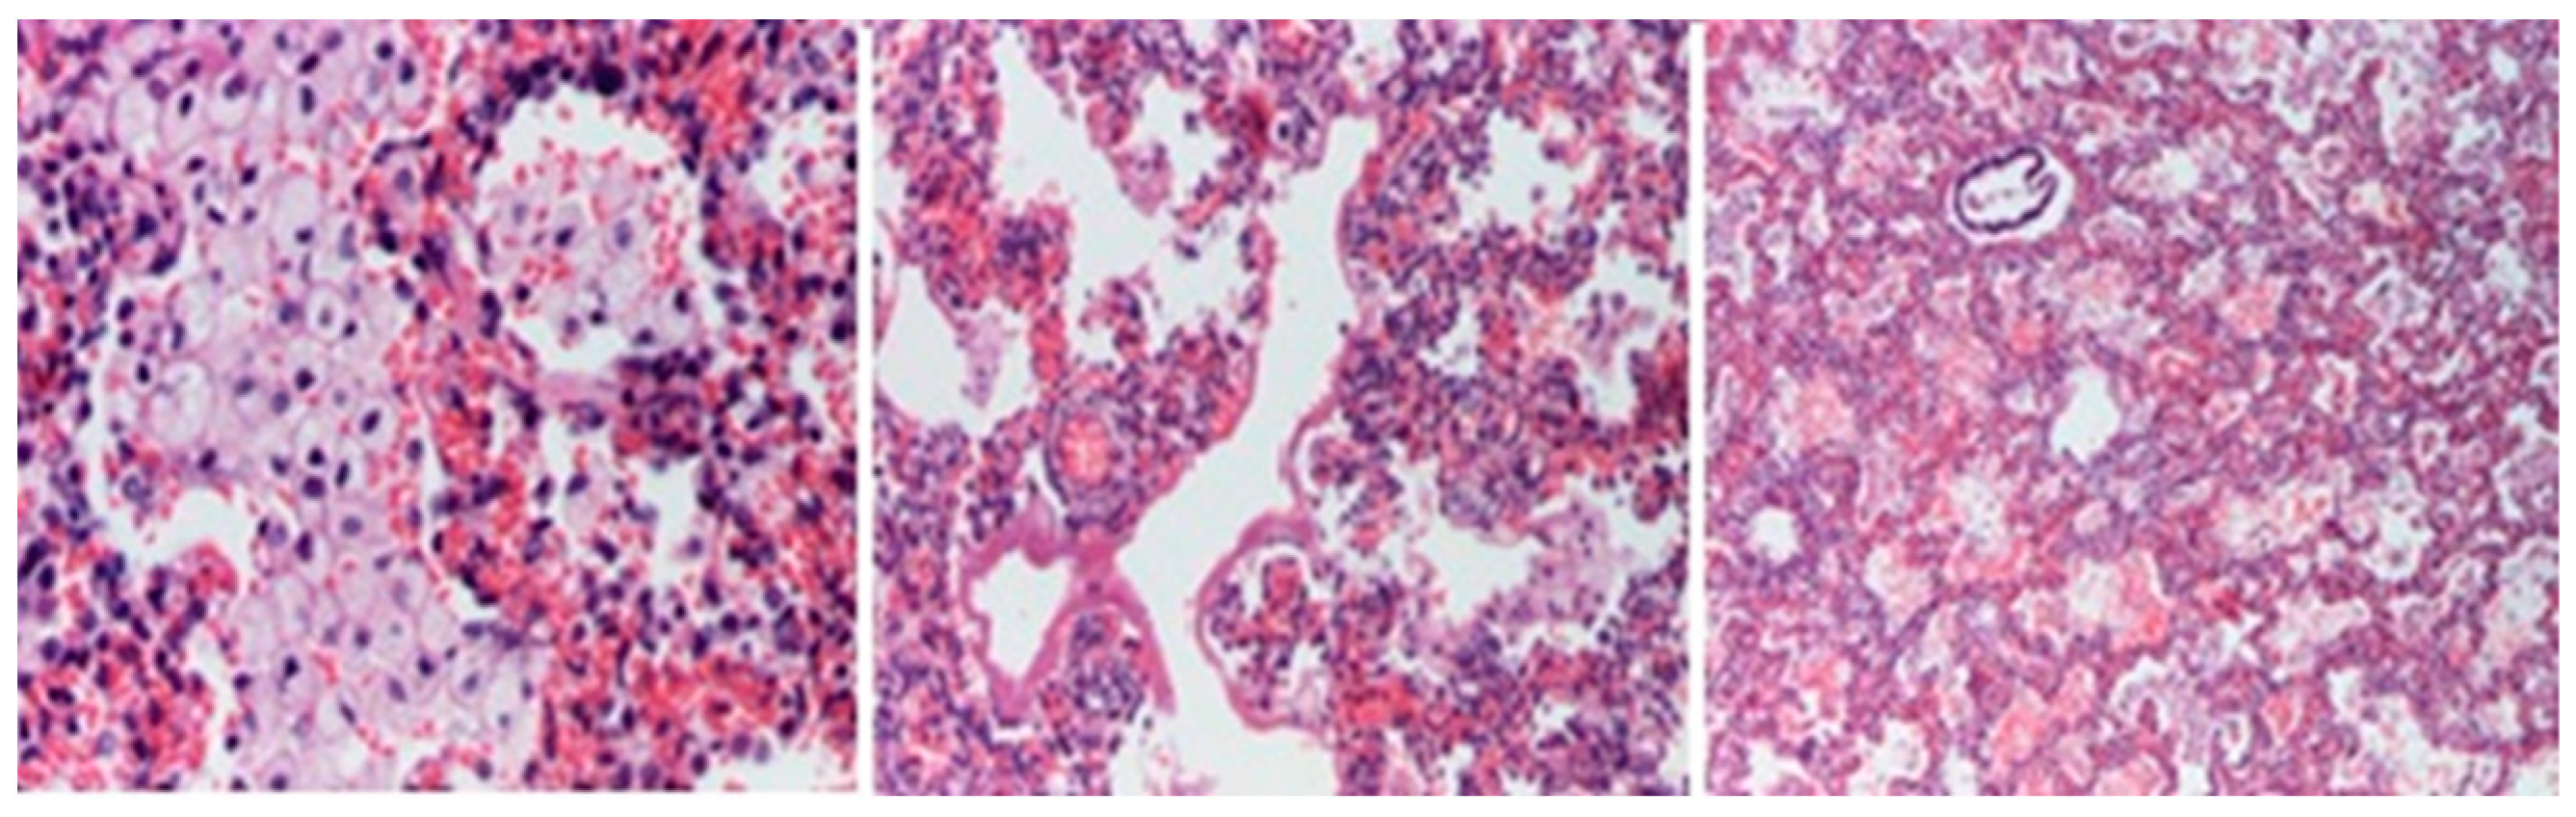

2. Case Report